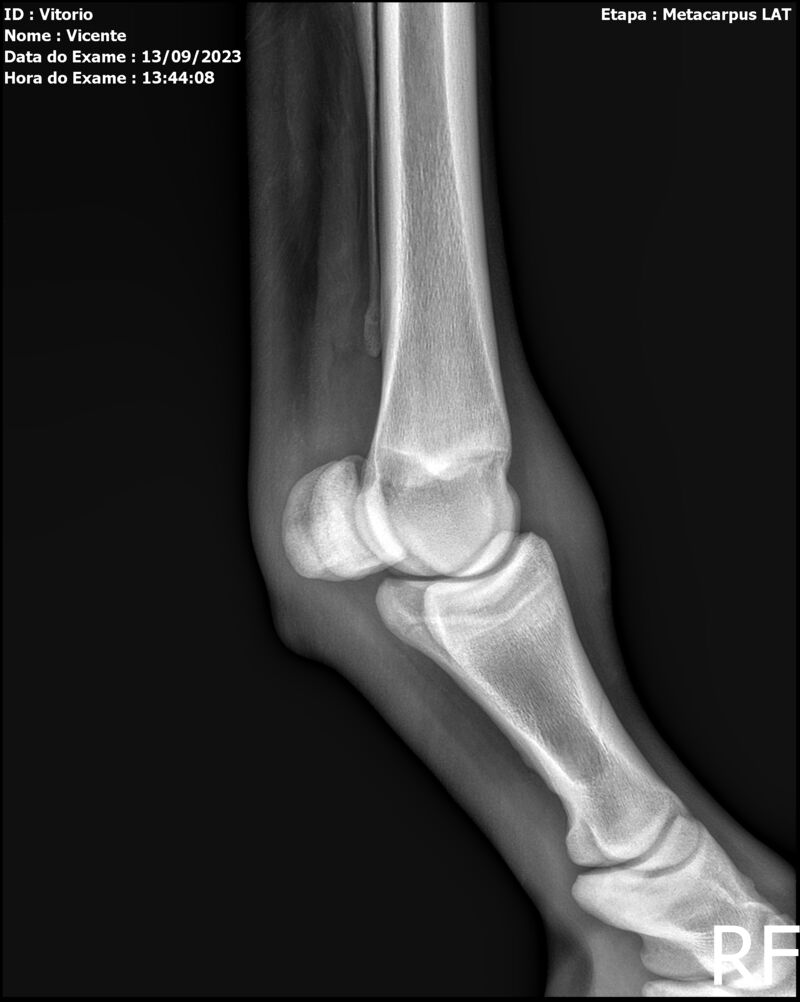

THUNDER ZC

Raça: BRASILEIRO DE HIPISMO

Sexo: MACHO - POTRO

Nascimento: 17/09/2022

Altura Aproximada: 1,54

Pel.: CASTANHO

Registro: EM AND

Vend.: VICENTE CONTE

Local : PORTO FELIZ/SP